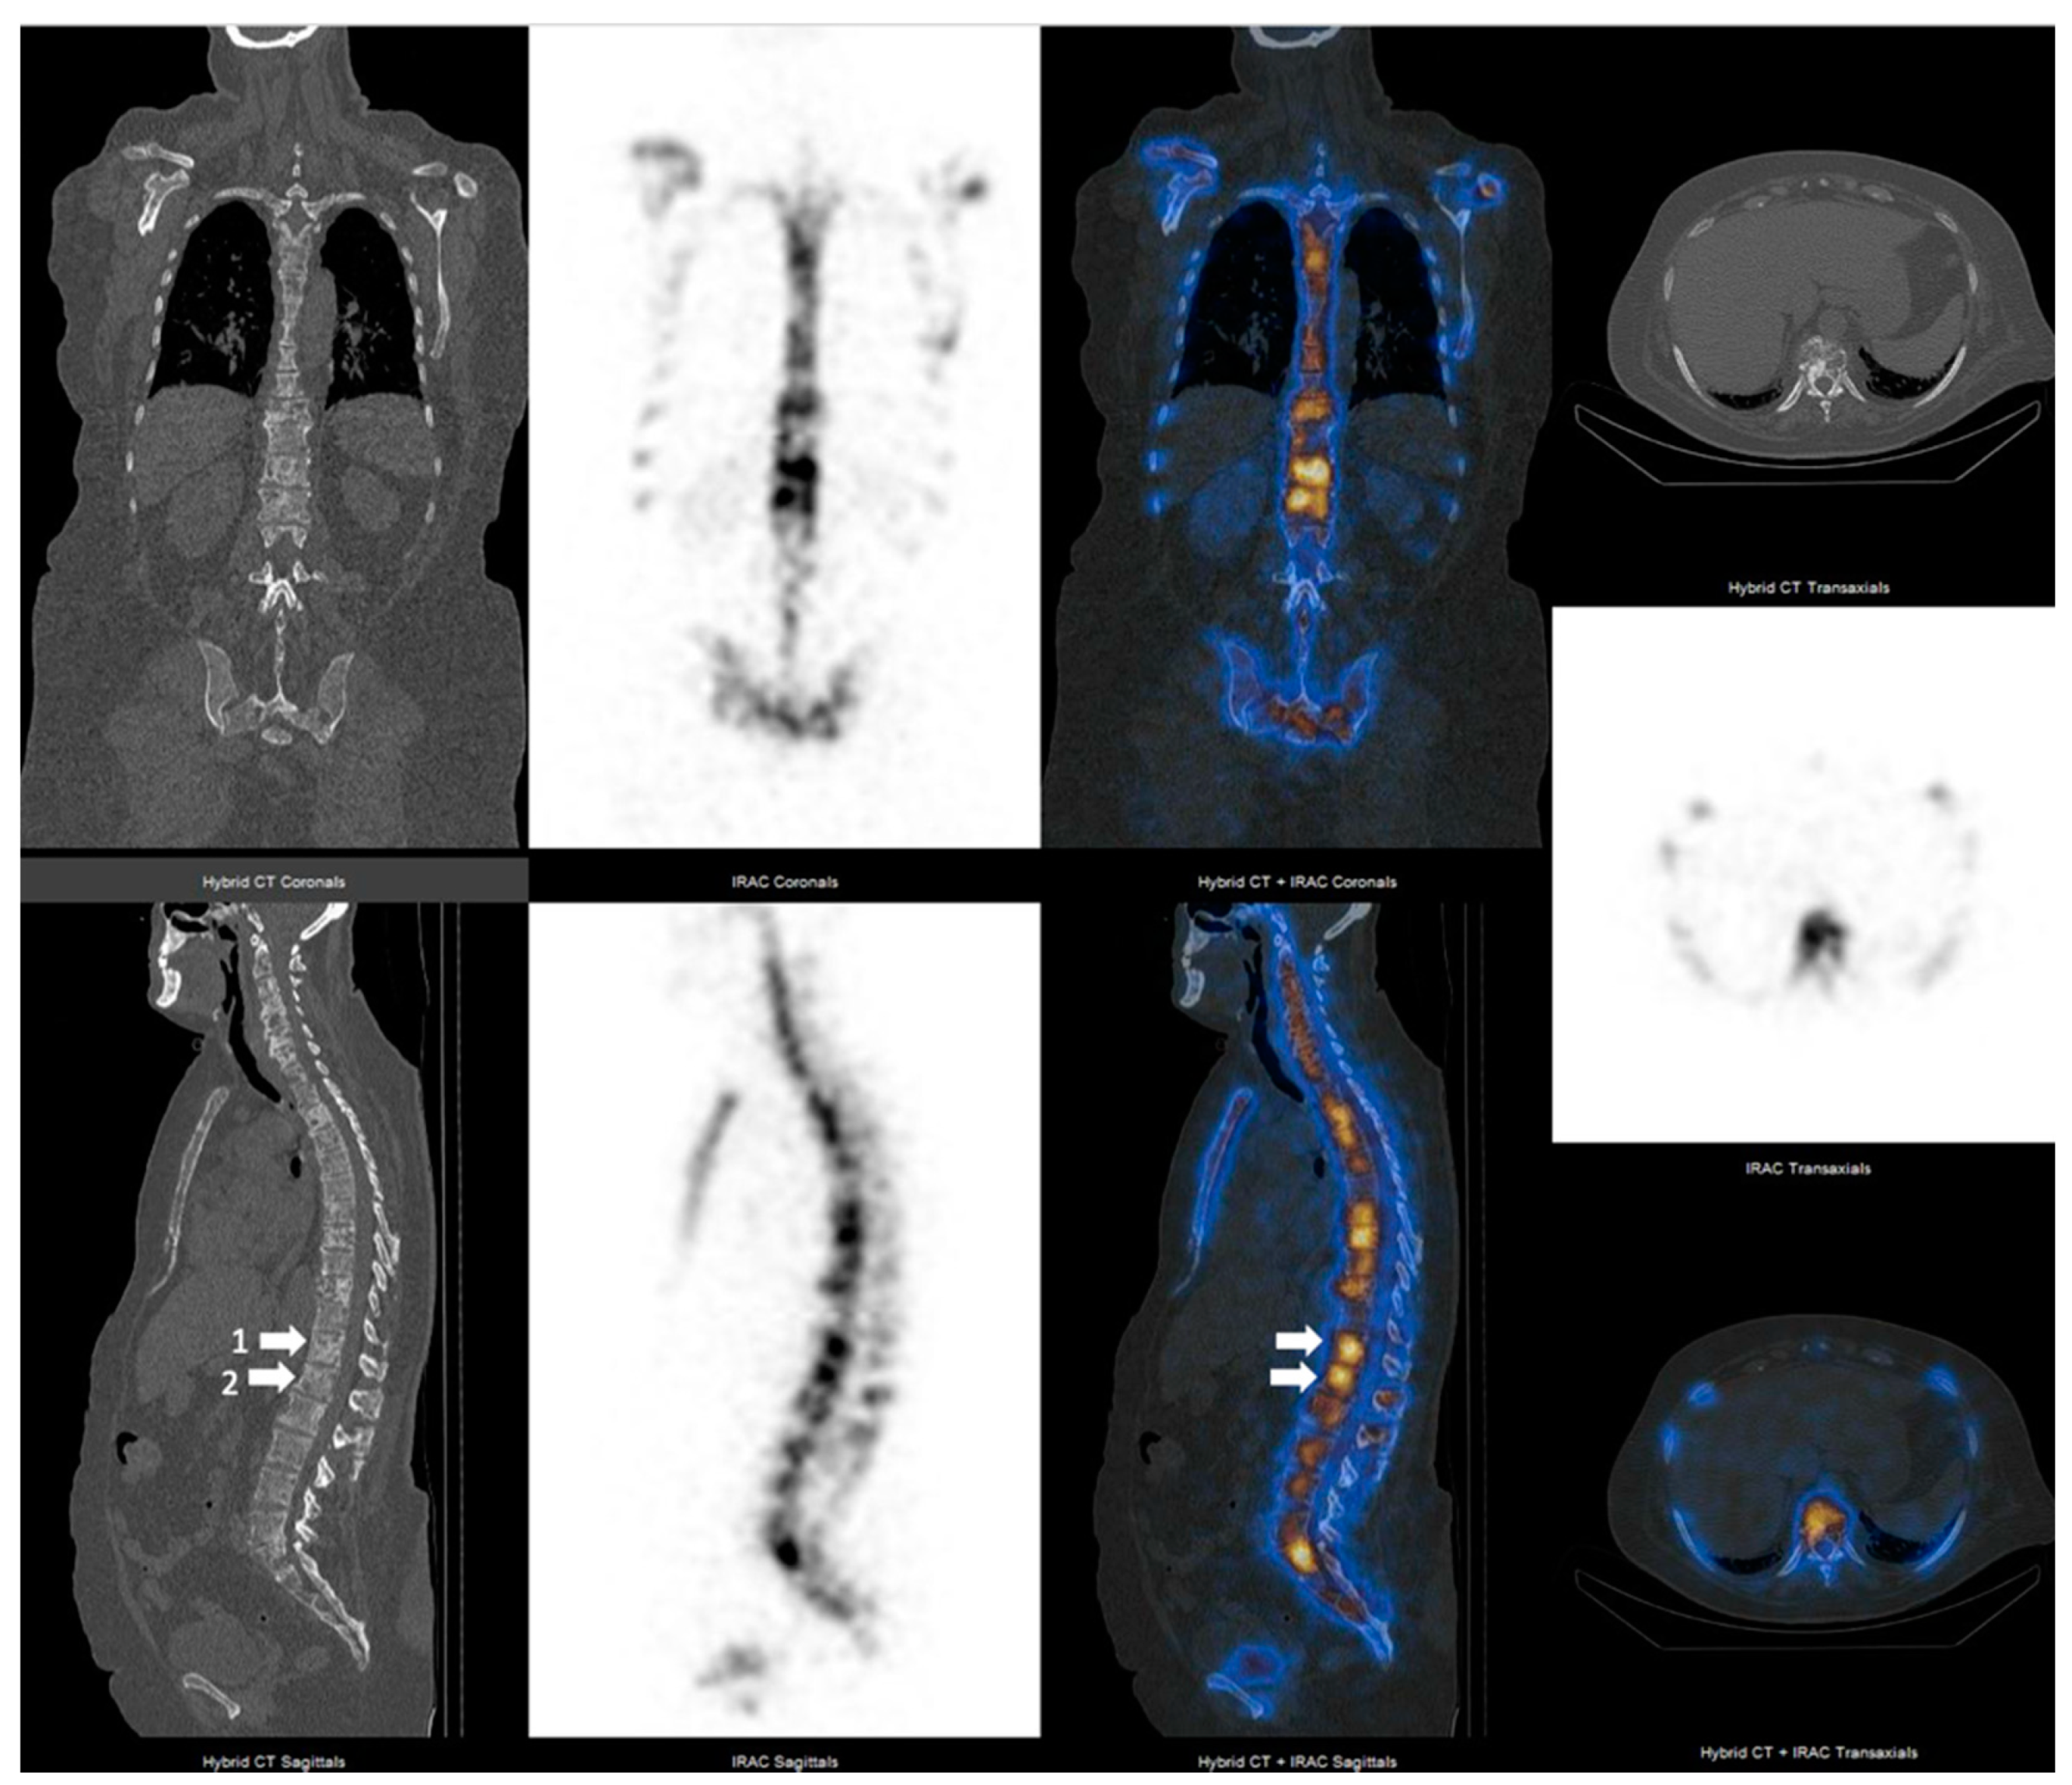

3.2. SPECT-CT SUVmax in Metastatic Lesions and Degenerative Bone Disease

3.3. SUVmax Cutt-off Value in Differentiating between Degenerative and Metastatic Lesions

3.4. SUVmax Overlapping